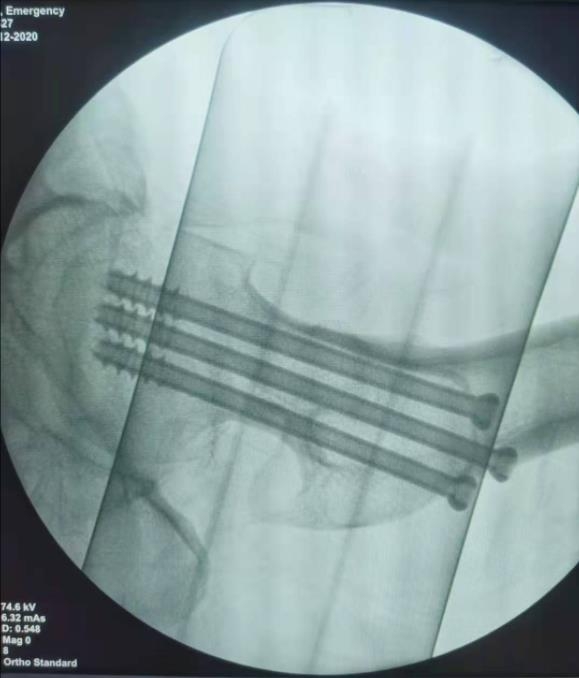

闭合复位经皮固定手术步骤

1、经皮沿股骨颈轴线置入空心钉导针,确保导针平行;

2、标准放置螺钉为倒三角形,其中下方螺钉在股骨矩,后方螺钉在后方骨皮质、研究发现倒三角形平行三枚螺钉能提供最佳的固定强度;

3、螺钉位于股骨颈四周,特别是后侧及下方,避免低于小转子方向进针,可能导致术后转子下骨折;

4、两个平面透视导针位置良好后切开皮肤,空心钻铭孔,导针引导下拧入空心钉,空心钉确保所有螺纹位于骨折线近端,螺钉头应距离软骨下骨5mm。

空心钉固定的三原则:“贴边、平行、倒品”。

1、贴边是指3枚螺钉在股骨颈内,尽量靠近外围皮质。这样3枚螺钉作为一个整体,对整个骨折面可形成面状加压,如果3枚螺钉不够离散,更趋于点状加压,稳定性较差,不能较好地对抗扭转和剪切。

有研究显示,在侧位片上,螺钉的前后分布越分散,骨折不愈合发生率越低。J Bone Joint Surg Br. 2005 May: 87(5): 632-4.

图1 3枚螺钉在股骨颈内的理想位置

3、平行生物力学更稳定。